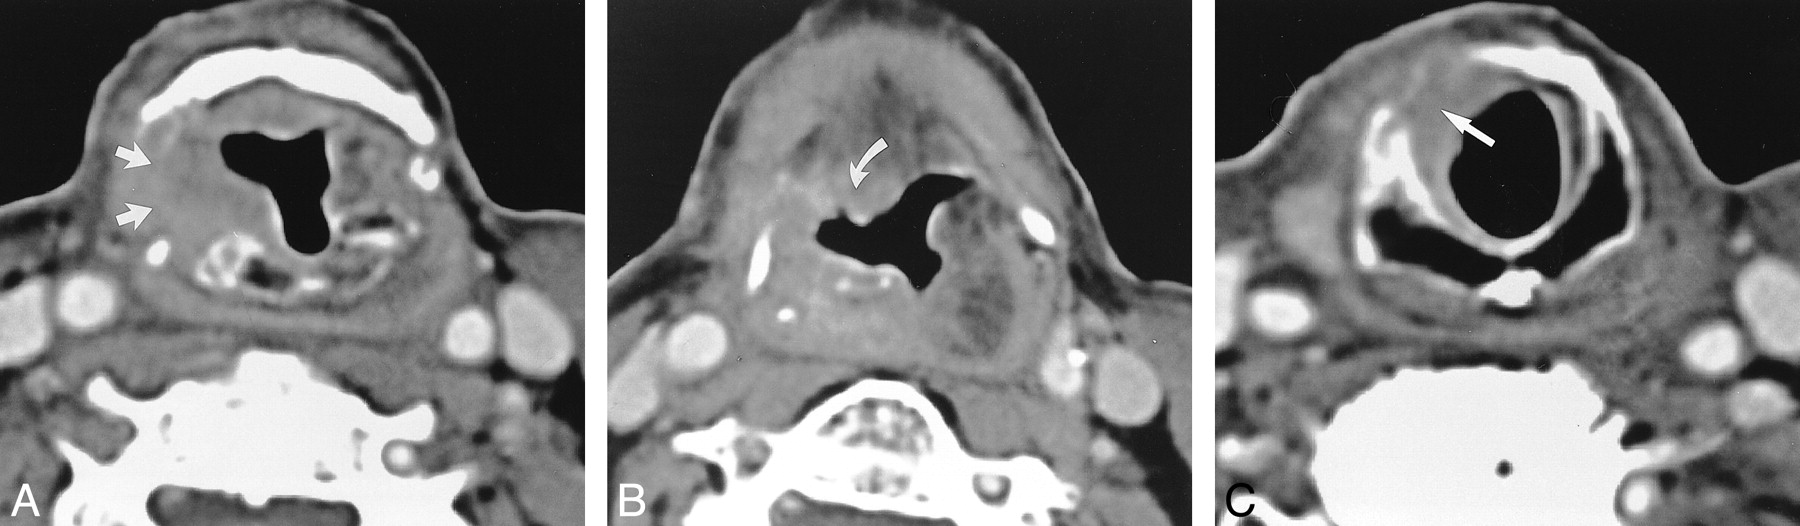

fig. 9. Axial CT scans of recurrrent disease in a patient who underwent SCPL with CHEP 2 y before.

A, Image depicts strong enhancement (star) of the right NAF compared with that of the left. This finding is very suggestive of recurrence.

B, The enhancement follows the lateral wall of the neovestibule (arrowheads). C, The enhancement proceeds down to the cricoid cartilage mucosa, which is thicker than usual (straight arrow), with the extralaryngeal spread of tumor (curved arrow).